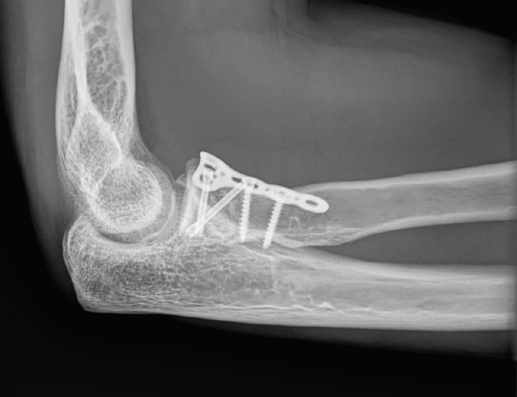

Son lesiones poco frecuentes pero complejas. Es esencial una reconstrucción anatómica precisa del cúbito proximal para recuperar la funcionalidad del codo. La restauración anatómica de la longitud y las dimensiones del cúbito será crucial para la congruencia de la articulación radiocapitelar. Una reconstrucción fallida o inadecuada acabará con dolor persistente y una progresiva degeneración de la articulación. Hay que poner especial atención en 2 fragmentos: la faceta anteromedial de la coronoides y la faceta anterolateral del cúbito, junto a la cresta del supinador. La planificación preoperatoria es vital, por lo que recomendamos la TAC con reconstrucción 3D (Figura 9).

Figura 9. A: imagen en 3D de una fractura proximal compleja de cúbito y radio; B y C: radiografías de control tras la cirugía en otro caso de lesión Monteggia-like.

Precisarán siempre tratamiento quirúrgico. Usaremos un abordaje posterior extendido. En las fracturas de Monteggia, el radio recupera normalmente su congruencia una vez que hemos reducido la fractura del cúbito. En las lesiones complejas Monteggia-like, lo ideal es reducir primero el fragmento de coronoides al fragmento cubital distal, ya sea con AK temporales o añadiendo algún tornillo adicional. Es el contrafuerte anterior de la articulación y de más difícil acceso. Luego fijaremos el resto de los fragmentos a la diáfisis con una placa preconformada LCP(41,42,43). Trataremos la fractura de la cabeza del radio mediante osteosíntesis o preferiblemente con una prótesis. Por último, repararemos las lesiones ligamentosas con un anclaje si fuera necesario (Figura 9). Cuando la punta del olécranon es multifragmentaria, un solo tornillo no ofrece fijación suficiente, por lo que hay autores que proponen un cerclaje con sutura de alta resistencia desde el tendón del tríceps para reforzar la síntesis(44,45).